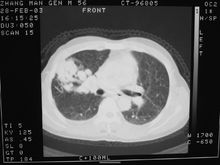

胸部PNB用以診斷肺臟、縱隔和胸壁病變,對肺內球形病籵及縱隔包塊的定性診斷有重要意義,準確率可達85%。較常見的併發症為氣胸、出血、但用細針的併發症甚少,腹部PNB套用較多,肝、膽、胰、脾、腎及腹後壁包塊均可,診斷準備性亦高;骨骼穿刺須用較粗骨穿針,可診斷骨腫瘤。此外還用於穿刺甲狀腺腫塊,眶內腫塊等等。

為保證針刺安全到達待查病變處,須用電視螢屏、CT、B超、及有關造影檢查,以便指引穿刺方向。